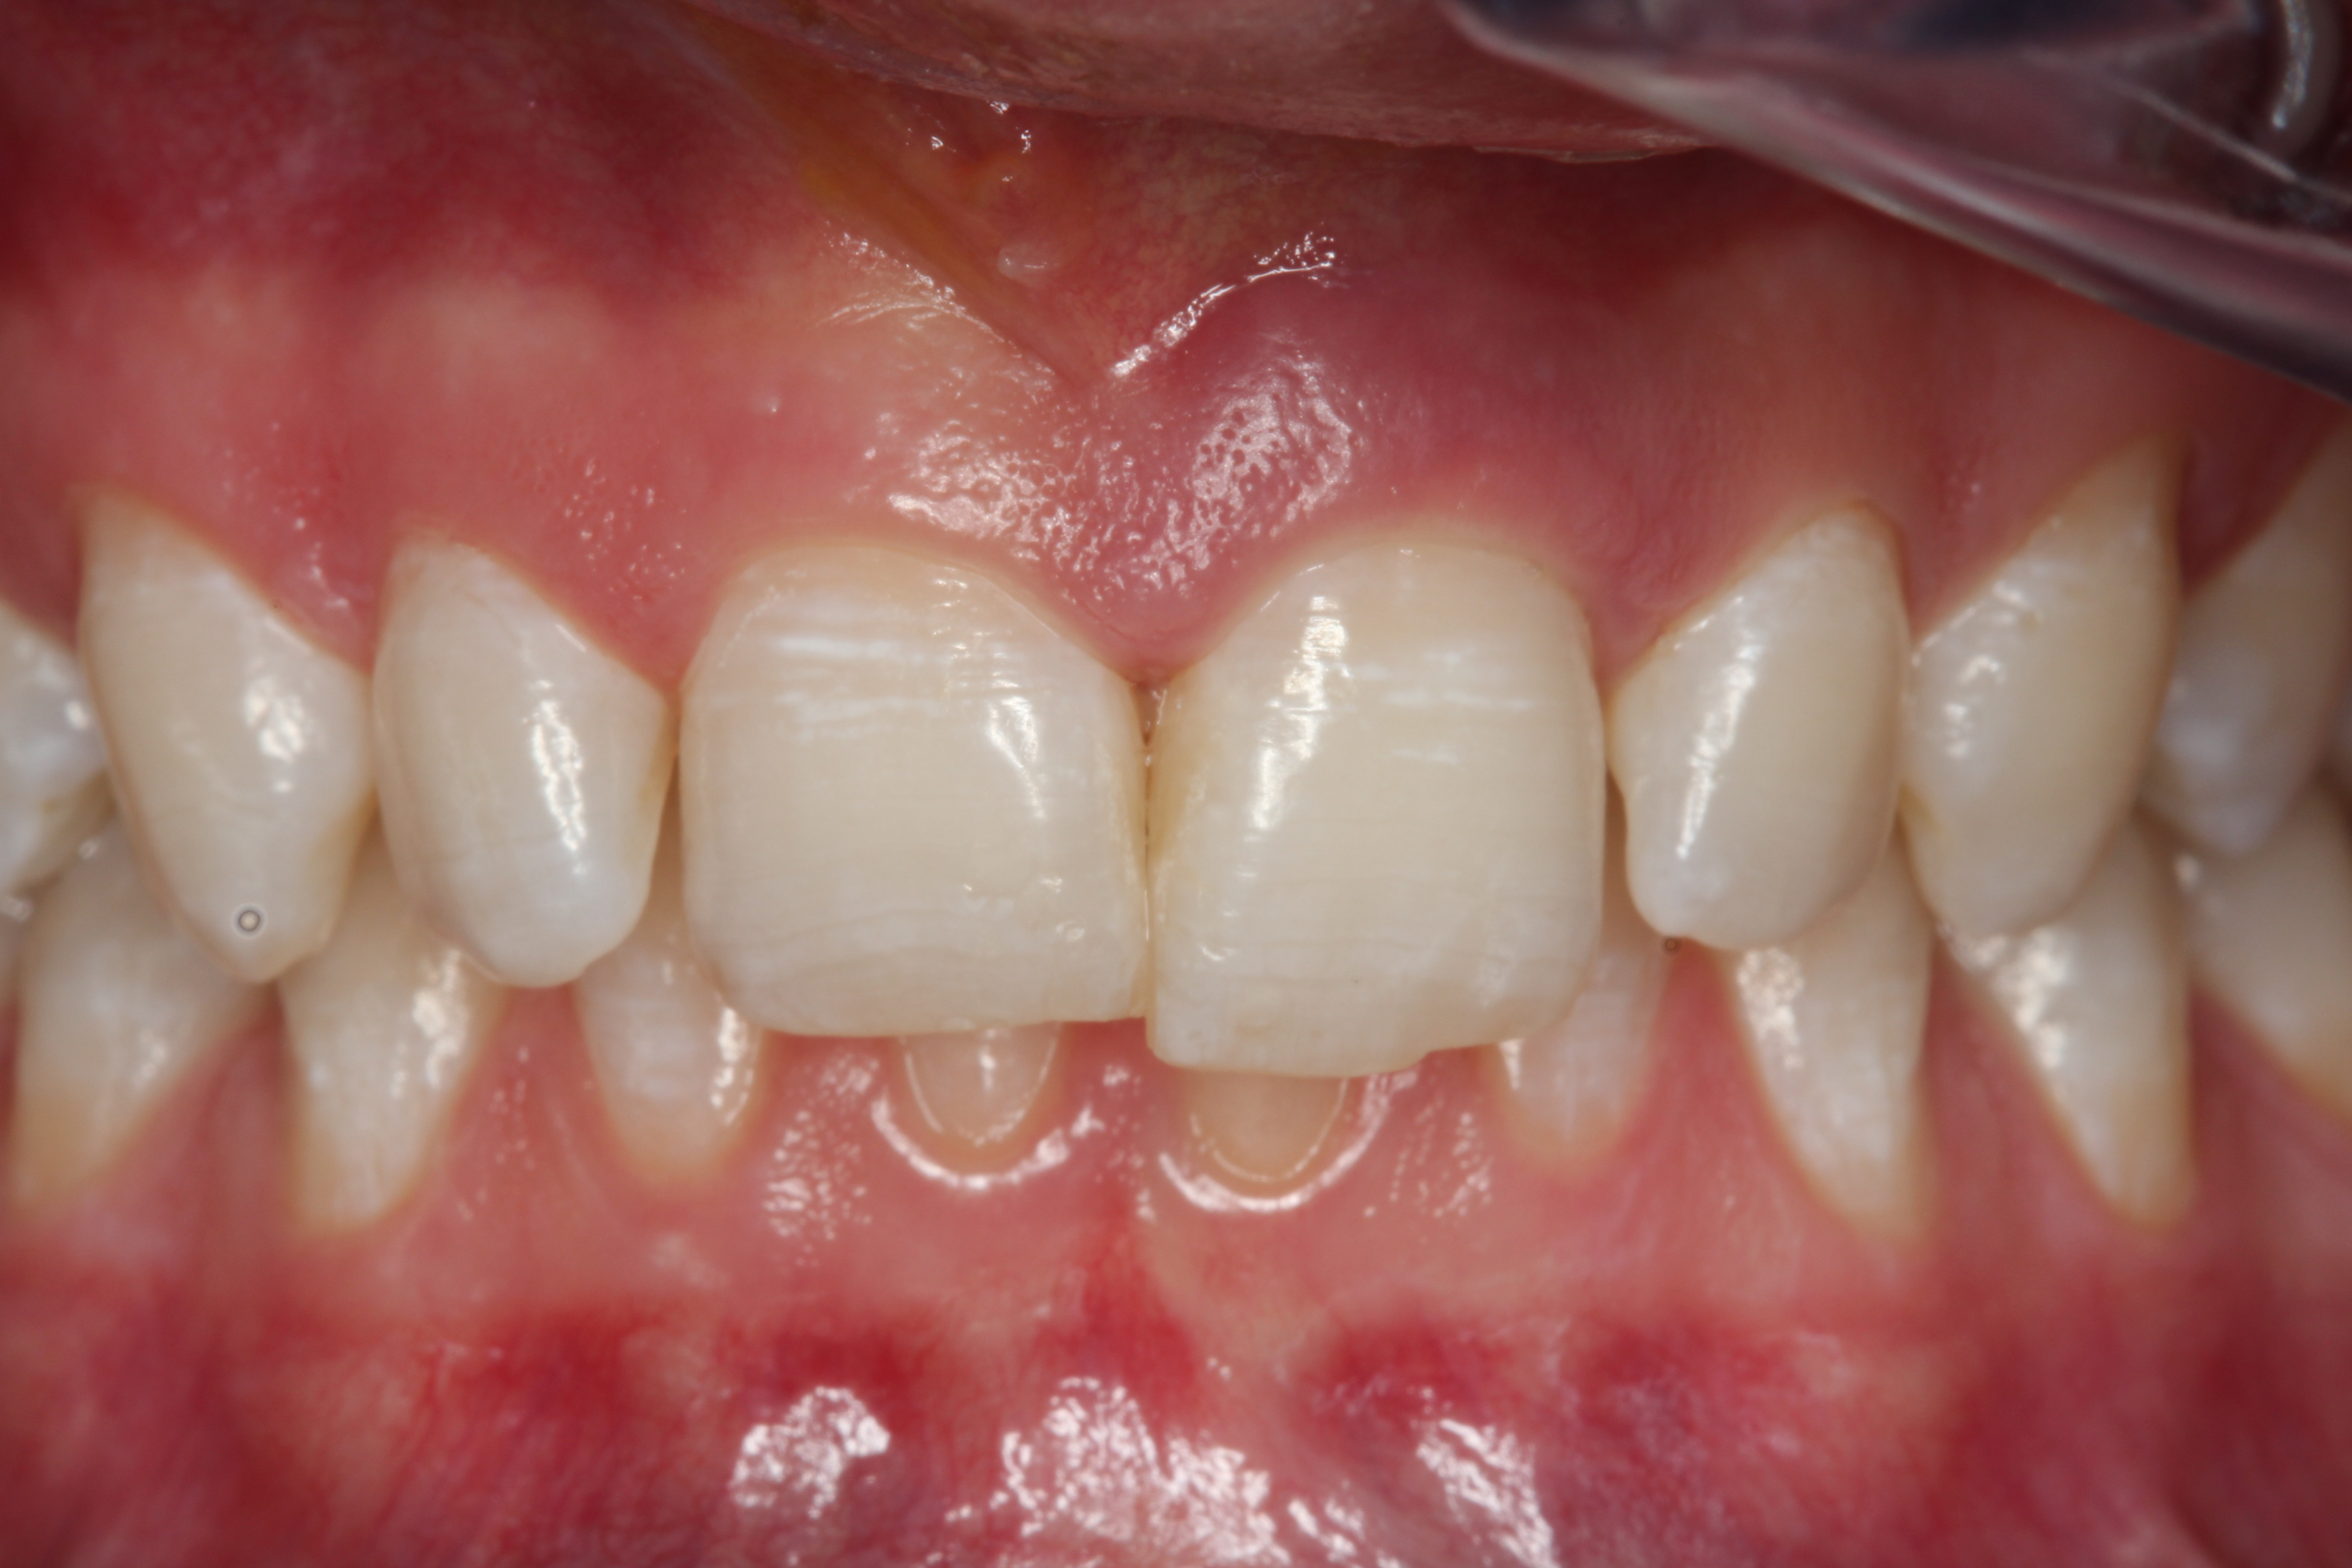

A young man presented with a fractured maxillary left-central incisor on a Monday morning after a Saturday evening discussion that did not end well (Figure 1). Visual oral examination and palpation of the structures revealed mobility of 3+, pain on palpation and percussion, a thick soft-tissue profile, and a low lip line. Gingival zeniths were irregular, there was a class II division 2 deep bite, and the periodontium was healthy overall (Figure 2 through Figure 4). Radiographs requested at the time of the initial visit were periapicals, panoramic, and CBCT images (Figure 5 and Figure 6). After all images and information were reviewed and the extent of his injury was discussed, the patient was presented with the following options: removable prosthetics, fixed partial denture, extract and do nothing, or extract and place a dental implant with bone augmentation.

Fig 2. Preoperative photograph after trauma.

Figure 2